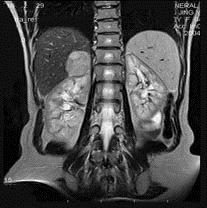

问题 男,31岁,体检时超声发现右肾上腺区病灶,MRI扫描如图所示,下列说法正确的是 ( )

选项 A、考虑为右侧肾上腺髓样脂肪瘤 B、考虑为右侧肾上腺嗜铬细胞瘤 C、该病灶在T1WI为等信号,在T2WI为稍高信号 D、考虑为右侧肾上腺腺瘤 E、右侧肾上腺区可见一类圆形病灶,与周围组织分界清楚

答案 CDE